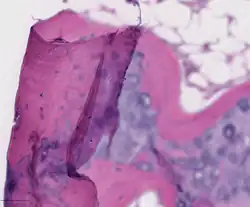

_stain_of_mixed_malignant_germ_cell_tumor_-_crop.png)

Digital pathology has been approved by the FDA for primary diagnosis.[47] The approval was based on a multi-center study of 1,992 cases in which whole-slide imaging (WSI) was shown to be non-inferior to microscopy across a wide range of surgical pathology specimens, sample types and stains.[48] As of mid 2025, approximately 50 digital pathology AIs have been cleared for primary diagnostic use (CE-IVD / CE-IVDR) in the EU.[49] While there are advantages to WSI when creating digital data from glass slides, when it comes to real-time telepathology applications, WSI is not a strong choice for discussion and collaboration between multiple remote pathologists.[50] Furthermore, unlike digital radiology where the elimination of film made return on investment (ROI) clear, the ROI on digital pathology equipment is less obvious. The strongest ROI justification includes improved quality of healthcare, increased efficiency for pathologists, and reduced costs in handling glass slides.[51]